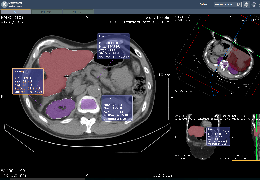

View X-Ray CT & MRI Scans Fast and Easily

Designed for surgeons, Pro Surgical 3D makes it easy to view patient scans quickly. Pro Surgical 3D facilitates the optimal 3D treatment and assessment workflows based on X-ray CT and MRI scans – and best of all, it’s FREE!

Performs 3D reconstruction and volume rendering.

Multi-planar slicing.

Oblique slicing.

Axis-aligned cropping with context.

Side-by-side comparative assessment for pre- and post-operative scans.